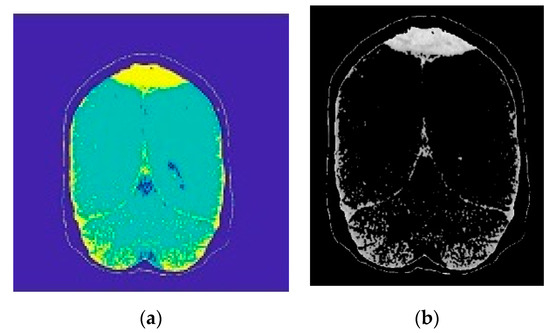

2.2.1. Image Segmentation

2.2.2. Morphological Operations